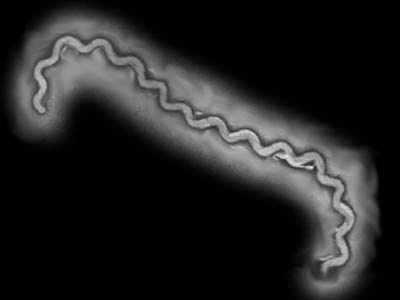

A enfermidade é causada pela Leptospira, uma bactéria aeróbia ou microaerófila, Gram-negativa, pertencente a ordem das espiroquetas. À microscopia observa-se morfologia em espiral, e freqüentemente um "gancho" nas extremidades da célula bacteriana. A leptospira não se multiplica fora do hospedeiro, e sua sobrevivência fora dele depende das condições do meio ambiente, sendo altamente sensível a ambientes secos e a pHs e temperaturas extremas. O patógeno pode sobreviver no meio ambiente por até 180 dias quando em solo úmido ou em águas paradas.

A enfermidade é causada pela Leptospira, uma bactéria aeróbia ou microaerófila, Gram-negativa, pertencente a ordem das espiroquetas. À microscopia observa-se morfologia em espiral, e freqüentemente um "gancho" nas extremidades da célula bacteriana. A leptospira não se multiplica fora do hospedeiro, e sua sobrevivência fora dele depende das condições do meio ambiente, sendo altamente sensível a ambientes secos e a pHs e temperaturas extremas. O patógeno pode sobreviver no meio ambiente por até 180 dias quando em solo úmido ou em águas paradas. Tradicionalmente o gênero Leptospira era subdividido em 200 sorovares, baseado nas diferenças antigênicas. Todos os sorovares patogênicos eram classificados como L. interrogans, e os não patogênicos eram incluídos na espécie L. biflexa. Atualmente, o gênero é classificado de acordo com suas características genéticas, em 7 genoespécies, 28 sorogrupos e vários sorovares e genótipos. O cão é o hospedeiro primário das espécies L. canicola e L. bataviae, geralmente associadas aos sintomas clínicos mais graves. Apesar de menos freqüente, o cão pode também ser um hospedeiro acidental das outras espécies de Leptospira, como L. gipptyphosa, L. pomona, L. icterohaemorrhagiae e L.bratislava .